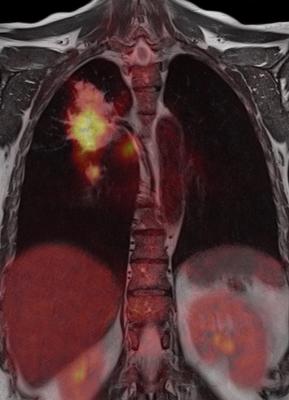

PET scans are expensive, but potentially powerful. They let doctors see increased activity by cells inside the body – including fast-growing cancer cells – and can do so early. Many cancer patients receive PET scans as part of diagnosis, to see how advanced their cancer is, and to see how it is responding to treatment.

But the scans are not recommended as the first option for long-term monitoring to watch for recurrence.